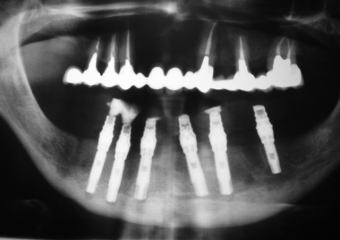

Imagem implantes inferiores em 2006 - Clínica Cliniface

Imagem implantes inferiores em 2006